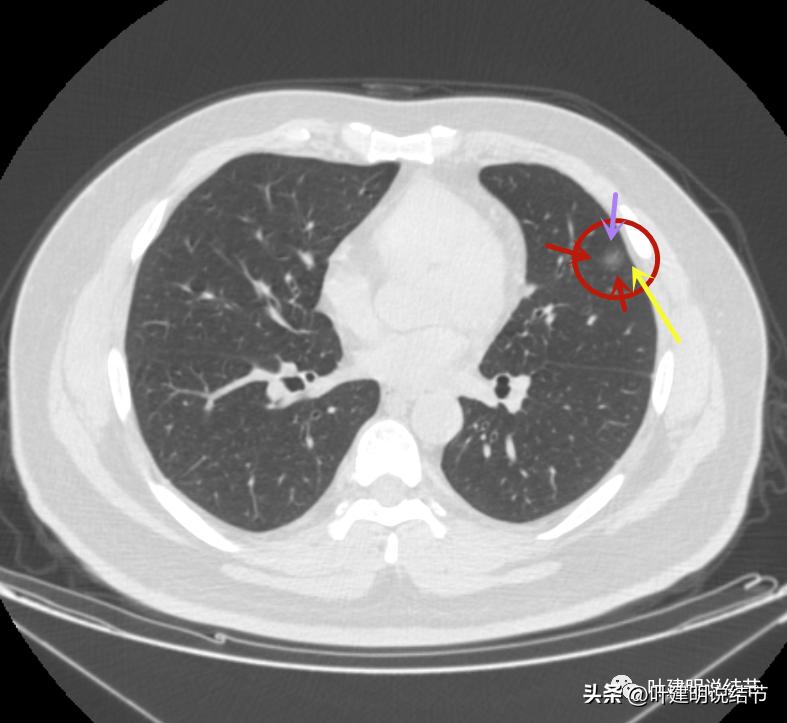

左上病灶4:舌段磨玻璃结节,边缘显力糊,整体轮廓较清,不典型增生可能性大点。

病灶出现,是淡磨玻璃影,但有微血管进入(桔色箭头)

密度稍不均,中间点状偏高密度,是不是血管?

周围微小血管好像有往病灶集中的趋势(桔色箭头)

病灶有胸膜间隙征(黄色箭头)、细毛刺样征(紫色箭头),整体轮廓较清(红色箭头)

轮廓清而密度稍不均,但总体仍应该算纯磨玻璃密度

有明显的血管穿行与细毛刺征

这个病灶也仍考虑是恶性范畴的,只是风险较病灶2与病灶3为低。也就是说看了细节与所有层面的信息,仍基本上认为四个病灶都是肿瘤范畴的,病灶1与病灶4大概浸润前病变可能性大,病灶2与病灶3则至少微浸润,基本以浸润性腺癌可能性大,不过不太能理解的有两点:一是病灶太集中;二是有的层面似有卫星灶。当然病灶2与病灶3感觉磨玻璃的成分偏少了些,也可作为疑惑之处。